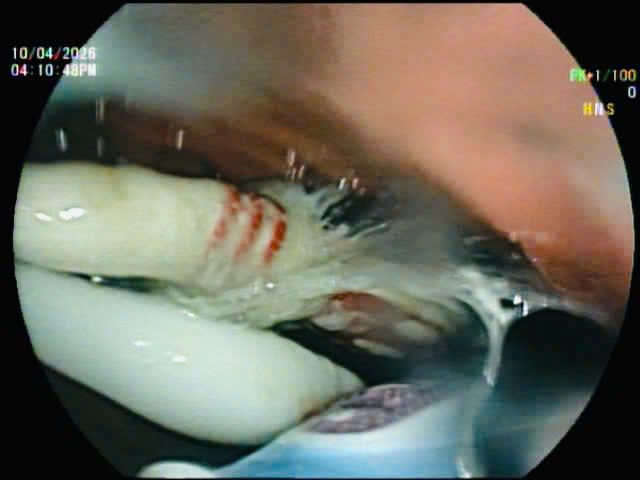

Hình ảnh 3 chiếc bàn chải đánh răng trong đường tiêu hoá của bệnh nhân qua hình ảnh nội soi.

Ngay sau khi tiếp nhận, bệnh nhân được chỉ định nội soi can thiệp. Ngày 10-4, đội ngũ ê-kíp đã tiến hành gắp thành công toàn bộ 3 bàn chải đánh răng ra khỏi đường tiêu hóa của bệnh nhân B. thuận lợi, không ghi nhận biến chứng.

Các bác sĩ nội soi gắp các bàn chải đánh răng ra khỏi đường tiêu hoá.